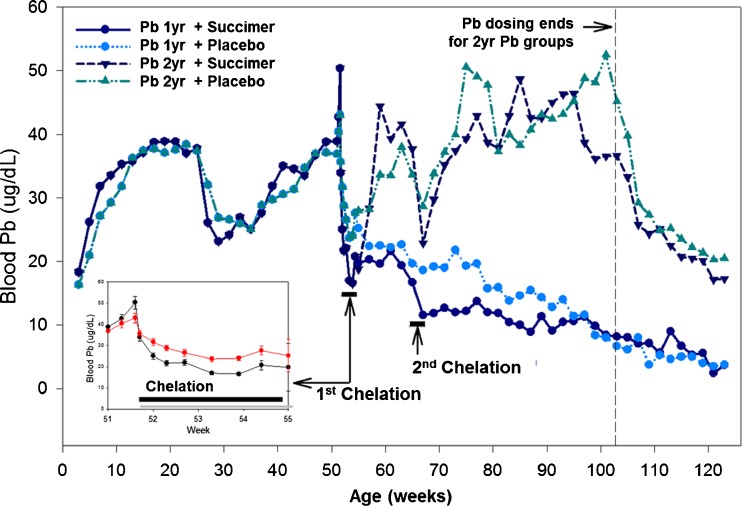

In Fig. 2 we show the blood lead profiles of animals administered oral lead for the first year of life. We want to point out that over the peri-weaning period blood lead levels dropped dramatically due to dietary changes (i.e., breast milk to solid food), similar to that which occurs in human infants. With this drop in blood lead levels, animals were administered higher doses of lead to bring their blood lead levels back to the target level of ∼40 to 45 mcg/dL. At 1 year of age, animals underwent their first chelation regimen—lead exposure ceased during chelation. After the first chelation regimen, animals remained off lead exposure (1 year lead-exposed groups) or were put back on lead exposure (2 years lead exposure groups) for their second year of life. A second chelation regimen was administered at age 65 weeks (Fig. 2).

Fig. 2.

Blood lead levels in the four groups of non-human primates receiving oral lead exposure for either the first 1 or 2 years of life. Each lead exposure group was divided into succimer or vehicle placebo groups, as indicated (n = 10–12/group). Inset panel shows expanded timeline over the first chelation regimen. (Smith et al. [11]). [Reprinted from Toxicology and Applied Pharmacology with permission from Elsevier]

Figure 3 shows the relative reduction in blood lead levels over the first course of chelation, with blood lead levels normalized to the starting (chelation day 0) blood leads of ∼43 to 50 mcg/dL in the two treatment groups. The data clearly demonstrate a reduction in blood lead levels with chelation, though notably the reduction is most dramatic over the first several days of treatment.

Fig. 3.

Mean ± SE blood total lead levels (as % of day 0 pretreatment values) in succimer and placebo-vehicle-treated 1-year lead-exposed monkeys over the course of the first chelation treatment (days 0–20) and beyond. Placebo and succimer group n = 21–23/group for days 24 to 20, and n = 11/group for days 24 to 60. (Inset) The mean ± SE integrated area under the curve (AUC; days 0 to 20) for the placebo vehicle and succimer groups. ***Statistically different (p < 0.001) from placebo group (comparisons performed only on treatment day 20 and on AUC data). For reference, blood lead levels on day 0 were 43 and 50 mcg/dL for the placebo and succimer groups, respectively (p = 0.08). Data from Smith et al. [11]. [Reprinted from Toxicology and Applied Pharmacology with permission from Elsevier]

It should be noted that while there is a dramatic drop in blood lead levels in the succimer-treated group with treatment, there is also a dramatic drop in the placebo-vehicle group, reflecting the efficacy of the cessation of lead exposure alone. However, when one looks at the integrated blood lead level over the treatment period, which is the area under the curve shown in Fig. 3, there is an overall substantial and significant reduction in blood lead in the succimer versus vehicle group, as expected. It is noteworthy, however, that there is a substantial rebound in blood lead levels in the succimer-treated group at the cessation of treatment, such that if one assessed chelation efficacy a few days after treatment ended, the data would indicate no measurable difference between the succimer and vehicle groups (Fig. 3). This raises the issue that assessment of chelation efficacy based on blood lead reduction may depend in part on when exactly blood lead levels are evaluated relative to chelation.